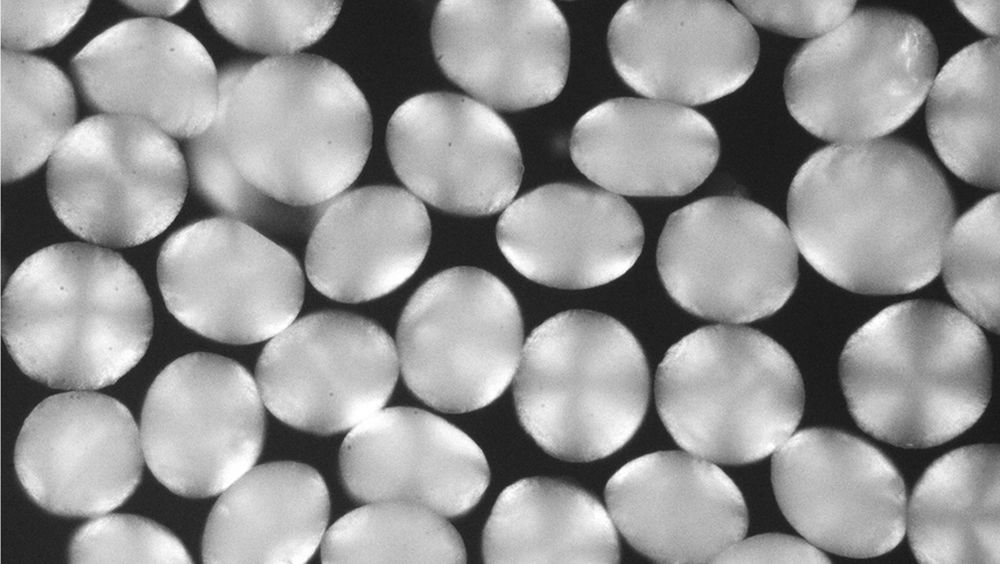

“Este compuesto es súper pegajoso y delicado, y necesitábamos encontrar alguna forma de que sus moléculas se movieran libremente dentro de una jeringa”, según Erfani. “La idea que tuvimos fue usar partículas de hidrogel, hechas de biopolímeros a base de azúcar, que es hidrófilo y que brindaron un ambiente agradable donde una proteína se desarrollaría bien”, asegura Doyle.

“Los habíamos usado para otras aplicaciones, y sabíamos que si podíamos hacerlo lo suficientemente pequeños, podrían atravesar una aguja sin obstruirla”. Además, el gel se dispersaba adecuadamente debajo de la piel.